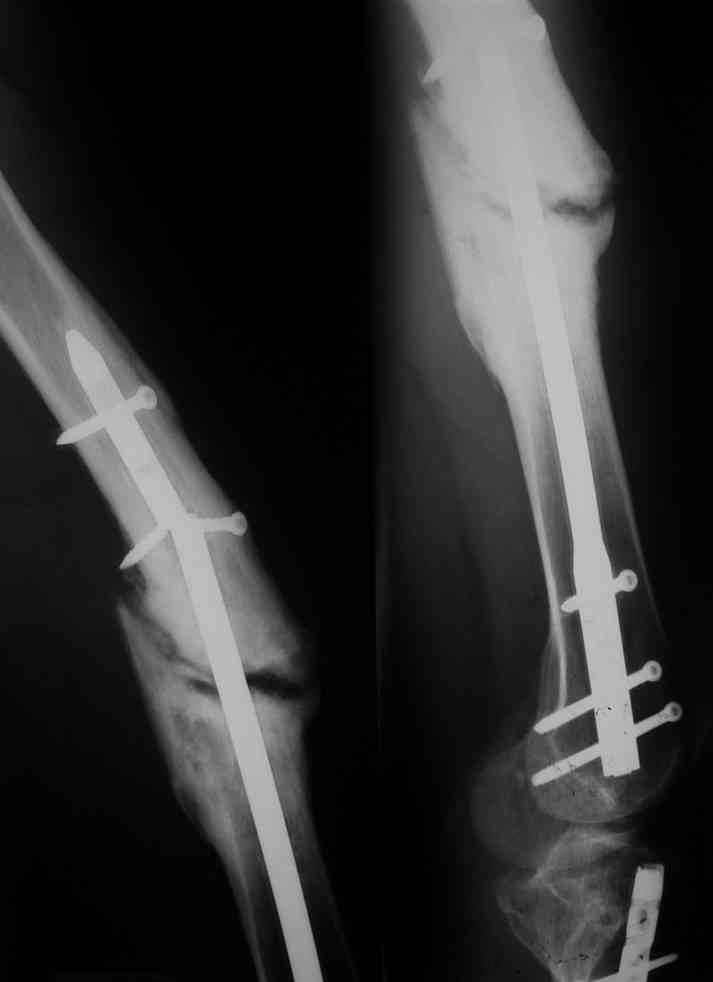

Одной рентгенограммы недостаточно, чтобы планировать подобную операцию. Вот похожий случай, который пришлось оперировать 3 мес. назад. Тоже короткий гвоздь. Шляпки винтов проксимального фрагмента полностью погружены в костную ткань, чего уже достаточно для необходимости обнажения этой зоны. У этого же больного оказались полностью разрушены шлицы 2-х дистальных винтов, так что и там нужно было "открываться".

Если получается удалить, рассверлить и пересинтезировать закрыто, то вмешиваться на зоне несращения тут не видно необходимости, концы отломков выглядят вполне оптимистично. Обнажение зоны несращения, скорее, как раз "дискредитирует" регенерацию.

Псевдоартроз выглядит нормо/гипертрофическим, если ось вас устраивает,можно обойтись стабилизацмей доступными вам способами без обнажения зоны псевдоартроза.удалить только проксимальный фрагмент гвоздя.